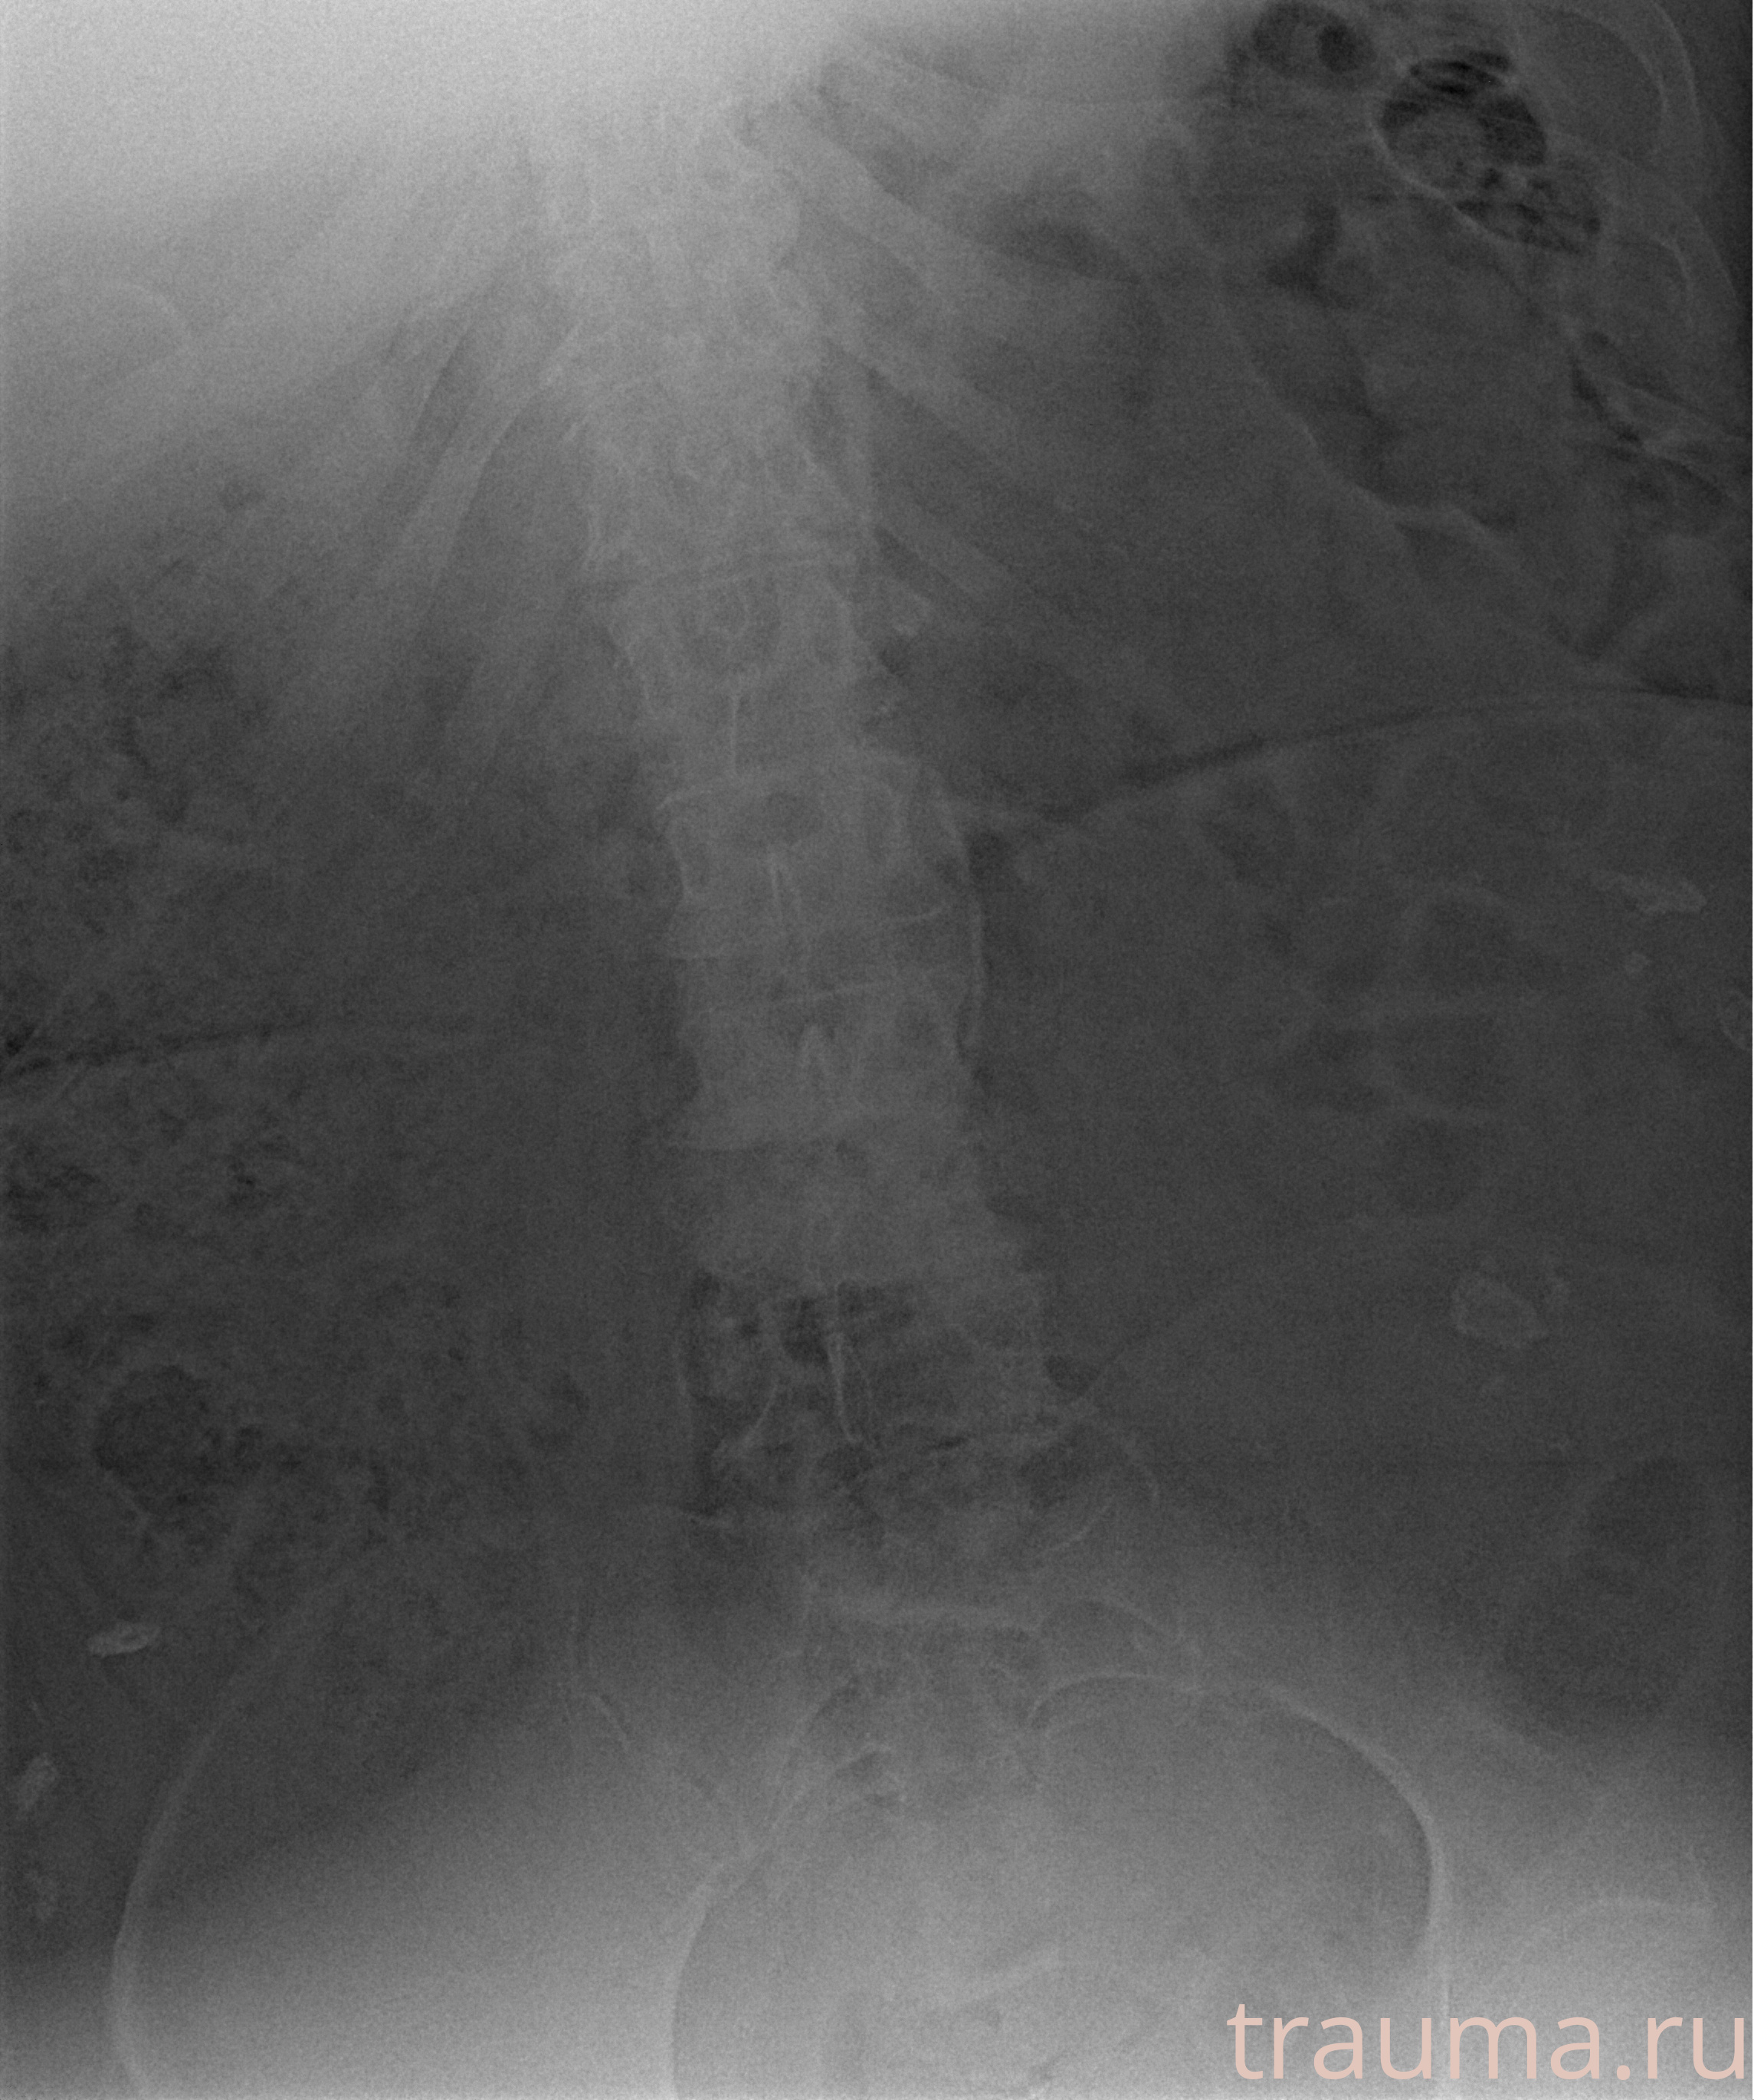

Рентген на дому: по вашему адресу приезжает врач-рентгенолог, травматолог-ортопед с мобильным рентгеновским аппаратом, проводит диагностику травмы или заболевания, делает необходимые рентгенограммы, дает рекомендации по дальнейшему лечению. Получить качественные снимки в домашних условиях возможно благодаря уникальной методике, разработанной МосРентген Центром для института  Склифосовского